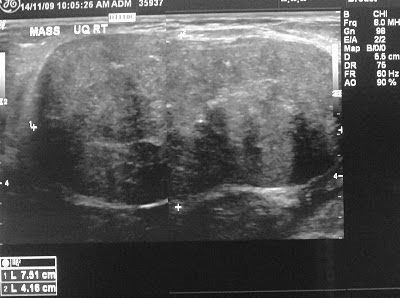

Pemeriksaan mamografi dan ultrasonografi (gambar II.03) umumnya penting dalam diagnosis lesi payudara, namun keduanya sangat tidak dapat diandalkan dalam membedakan tumor filoides jinak dari bentuk kondisi ganas ataupun dari fibroadenoma. Dengan demikian, temuan pada studi pencitraan bukanlah diagnosis pasti. Biopsi payudara eksisi terbuka untuk lesi lebih kecil atau biopsi insisional untuk lesi lebih besar adalah metode pasti untuk mendiagnosis tumor filoides.

Gambar II.03. Gambaran mammografi dari tumor filoides

Pada mammogram, tumor Phyllodes akan memiliki tepi yang berbatas jelas. Baik  mammogram ataupun USG payudara  dapat membedakan secara jelas antara fibroadenoma dan Phyllodes jinak atau tumor ganas. Jenis tumor payudara ini biasanya tidak ditemukan di dekat microcalcifications. Sel-sel dari biopsi jarum dapat diuji di laboratorium tapi jarang memberikan diagnosis yang jelas, karena sel-sel dapat menyerupai karsinoma dan fibroadenoma. Pada Biopsi bedah akan menghasilkan potongan jaringan yang akan memberikan sampel sel lebih baik dan akan menghasilkan diagnosa yang tepat untuk sebuah tumor Phyllodes.

Gambar 4. Gambaran mamografi cystosarcoma

MRI payudara dapat membantu tindakan operasi dalam pengangkatan jaringan tumor phyllodes. Sebuah studi membandingkan mammogram di Italia, USG dan MRI payudara dari tumor Phyllodes melaporkan bahwa MRI memberikan gambaran yang paling akurat dan ini membantu ahli bedah tumor dalam menjalankan rencana operasi mereka. Bahkan jika tumor itu cukup dekat dengan otot-otot dinding dada, payudara MRI bisa memberikan gambaran yang lebih baik dari tumor phyllodes daripada mammogram atau USG.

Gambar 5. Gambaran USG